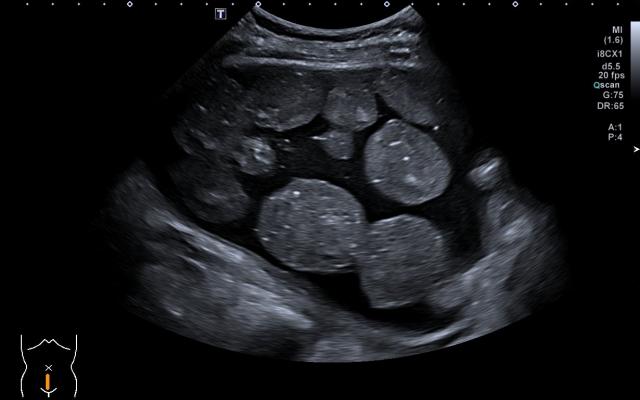

Een 55-jarige vrouw kwam op de polikliniek Heelkunde vanwege een progressieve zwelling in de hals. Bij lichamelijk onderzoek zagen wij een subtiele verhevenheid in de fossa jugularis. De zwelling was elastisch en mobiel en lag los van de huid. Echografie van de hals liet een scherp begrensde, echo-arme, zachte afwijking zien in de mediaanlijn caudaal van de schildklier (figuur a). De afwijking bevatte meerdere, perfect ronde bolletjes met een diameter van 0,5 cm, uniform in grootte en echogeniciteit, zonder aanwijzingen voor bloeddoorstroming (‘flow’). Op basis van dit bijzondere echobeeld dachten wij aanvankelijk aan corpora aliena. Een aanvullende CT-scan van…